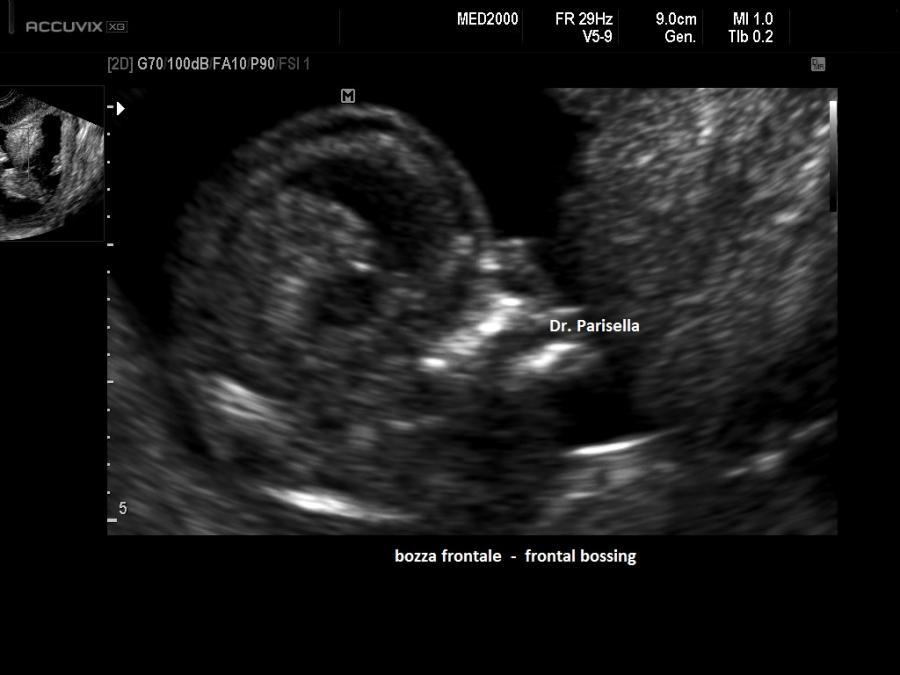

E' caratterizzata da un accorciamento prevalente del femore (rizomelia), anche se sono interessate tutte le ossa lunghe (micromelia) e le ossa delle mani e dei piedi (brachidattilia); la testa è grossa (macrocefalia/macrocrania) con bozze frontali prominenti e ponte nasale depresso. La diagnosi ecografica precoce non è possibile. Spesso infatti l'acondroplasia può essere sospettata o confermata solo in fase avanzata di gravidanza in quanto la micromelia si manifesta tardivamente con un accrescimento delle ossa lunghe inferiore al 5° percentile evidente solo nel III trimestre. La diagnosi può essere facilitata in caso di storia familiare positiva per tale patologia. Alcuni studi hanno riportato l'associazione con la NT aumentata.

3.    Bozze frontali sporgenti